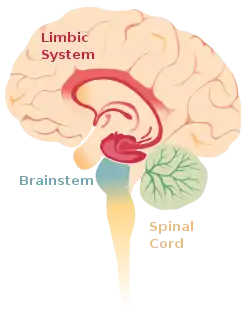

| The limbic system within the brain. | |

Limbic encephalitis is a form of encephalitis, a disease characterized by inflammation of the brain.[1] Limbic encephalitis is caused by autoimmunity: an abnormal state where the body produces antibodies against itself. Some cases are associated with cancer and some are not.[1] Although the disease is known as "limbic" encephalitis, it is seldom limited to the limbic system and post-mortem studies usually show involvement of other parts of the brain.[2][3][4] The disease was first described by Brierley and others in 1960 as a series of three cases. The link to cancer was first noted in 1968[3] and confirmed by later investigators.[5]